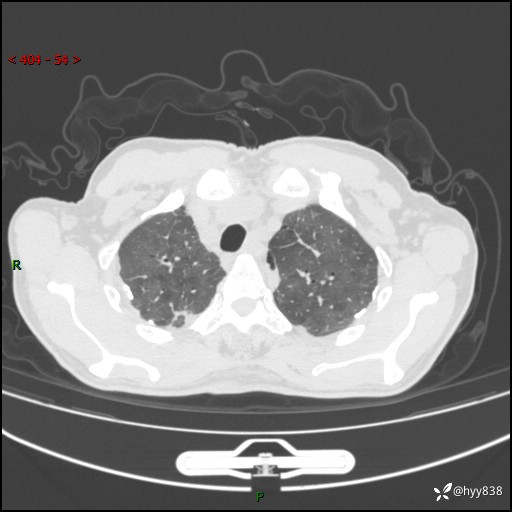

辅助检查:CT

胸部CT平扫